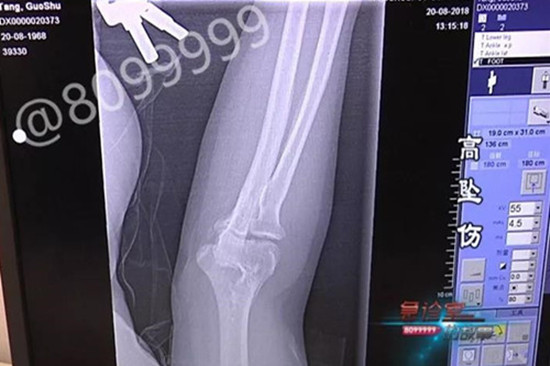

医院的两位骨科专家,对其伤情进行了会诊。经过骨科专家的初查,排除了致命的颅脑出血,但是罗师傅下颌骨、颈椎、肋骨,都出现了粉碎性骨折的情况。

小张在一栋民房楼顶施工时,没有做安全防护措施,脚底一滑,从9米多高的楼顶坠落。造成肘关节骨折,肱骨远端骨折,腰椎骨折,股骨骨折。虽然手术很顺利,但还需休息3个月才能逐渐恢复健康。